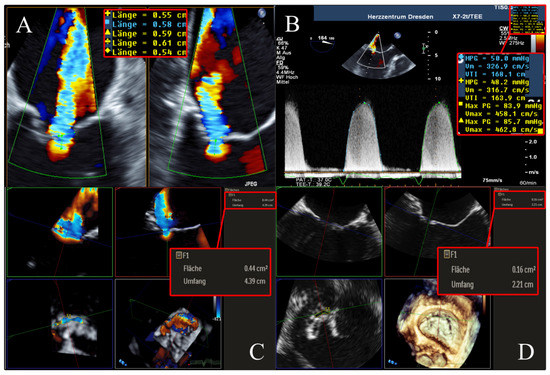

To determine the EROA using 2D PISA, biplane 2D color Doppler images (X-Plane views) were acquired optimally at a Nyquist velocity between 20 and 45 m/s. In the TEE 4-chamber view as well as in the orthogonal section plane with maximal expression of proximal convergence, the radius of proximal convergence between color change and plane of coaptation defect (minimal regurgitation area) was measured in mid-systole over different heartbeats. In addition, the maximum regurgitation velocity (MR-Vmax) and velocity–time integral (MR-VTI) in systolic phase of CW Doppler recordings were determined (Figure 2). Using the PISA method, the EROA was calculated according to the recommendations of the European Association of Cardiovascular Imaging (EACVI) [2].

Figure 2. Determination of 2D PISA in biplane 2D color Doppler dataset and CW Doppler dataset. Echocardiographic images with 2 orthogonal slice planes of the 2D color Doppler dataset (mid-systolic) with Nyquist velocity of 38.5 cm/s (left); determination of PISA radius in 2 planes (diameters with crosses), MR-VTI (dotted outline), and MR-Vmax in the CW Doppler dataset (right) for calculation of regurgitation area. Abbreviations: 2D = two-dimensional; PISA = proximal isovelocity surface area; CW = continuous wave; MR-VTI = mitral regurgitation velocity–time integral; MR-Vmax = maximum mitral regurgitation velocity.

The AROA was measured by subtracting the color from the full-volume 3D color Doppler datasets. The AROA was planimetrically adjusted to the minimum cross-sectional plane of the anatomic regurgitation defect between the mitral valve leaflets (Figure 4). The area of the minimal anatomic regurgitation defect was measured by tracing the boundary of the leaflets. Analogous to the measurement of the 3D VCA, settings for brightness and contrast were fixed at 50% values and smoothening.

Figure 4. Determination of AROA using multiplanar reconstruction of the 3D color Doppler dataset without color. Echocardiographic images with 3 slice planes and 3D reconstruction (lower right) of the 3D color Doppler dataset (mid-systolic) with subtraction of color. Planimetric fitting of the 2 upper planes along the course of the color Doppler jet; third plane (lower left) adjustment orthogonal to planes along the jet. Then, subtraction of color and finding the minimum coaptation defect between the mitral valve leaflets using translation and tilting of the third plane; manual measurement of the minimum coaptation defect using outlining. Abbreviations: AROA = anatomical regurgitation orifice area; 3D = three-dimensional.

To facilitate a better understanding of our subsequent results of the cross-method comparisons, we illustrate in Figure 5 a representative example of the same patient evaluated for FMR using the 3D VCA, AROA, and EROA 2D PISA.

Figure 5. Example of a 51-year-old, male patient suffering from FMR due to non-ischemic dilated cardiomyopathy. (A,B) ERO quantified using 2D PISA method was 0.20 cm2, with a mean MR-Vmax of 460 cm/s. (C) 3D VCA derived by multiplanar reconstruction in a 3D color Doppler dataset was 0.44 cm2. (D) AROA derived by multiplanar reconstruction in a 3D Doppler dataset without color was 0.16 cm2. Abbreviations: FMR = functional mitral valve regurgitation; 2D = two-dimensional; PISA = proximal isovelocity surface area; CW = continuous wave; MR-Vmax = maximum mitral regurgitation velocity; 3D = three-dimensional; VCA = vena contracta area; AROA = anatomical regurgitation orifice area.